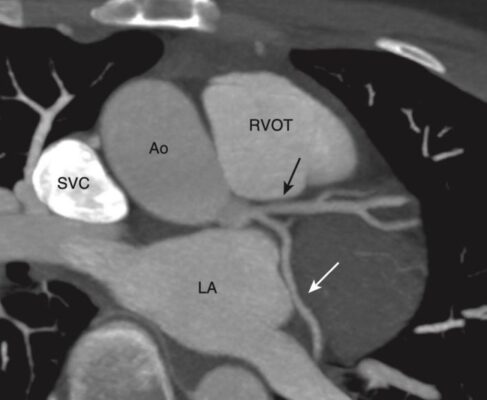

Mức cửa sổ chủ phế (Aortopulmonary Window) (Hình 7)

- Ở mức này, có thể xác định được động mạch chủ lên và xuống, tĩnh mạch chủ trên và (có thể thấy) mặt trên của động mạch phổi trái .

- Khi các lát cắt xuống thấp hơn qua lỗ mở chữ U lộn ngược của cung động mạch chủ, động mạch chủ lên sẽ có dạng tròn ở phía trước, trong khi động mạch chủ xuống sẽ có dạng tròn ở phía sau và bên trái của cột sống. Động mạch chủ lên thường có đường kính 2,5 đến 3,5 cm và động mạch chủ xuống nhỏ hơn một chút ở mức 2 đến 3 cm.

- Ở hầu hết mọi người, có một khoảng trống ngay bên dưới cung động mạch chủ nhưng ở trên động mạch phổi được gọi là cửa sổ chủ phế. Cửa sổ động mạch chủ là một mốc quan trọng vì đây là vị trí thường xuất hiện các hạch phì đại.

- Ở mức này hoặc thấp hơn một chút, khí quản chia đôi ở carina thành phế quản chính phải và bên trái.

Hình 7. Mức cửa sổ chủ phế (A) và hình cắt đứng bên (vành/trán) (B). A, Ở mức này, có thể xác định được khí quản (T), động mạch chủ lên (AA) và động mạch chủ xuống (DA), tĩnh mạch chủ trên (S), và có thể là mặt trên của động mạch phổi trái (P), cửa sổ chủ phế (mũi tên trắng). B, CT đứng bên được định dạng lại cho phép chúng ta nhìn thấy cả tâm nhĩ phải (RA), tĩnh mạch chủ trên (S), tâm thất trái (LV), van động mạch chủ (mũi tên đen), động mạch chủ lên (AA), động mạch phổi chính (P), phần phụ tâm nhĩ trái (mũi tên màu trắng), và gốc của các mạch máu lớn (vòng tròn màu trắng).